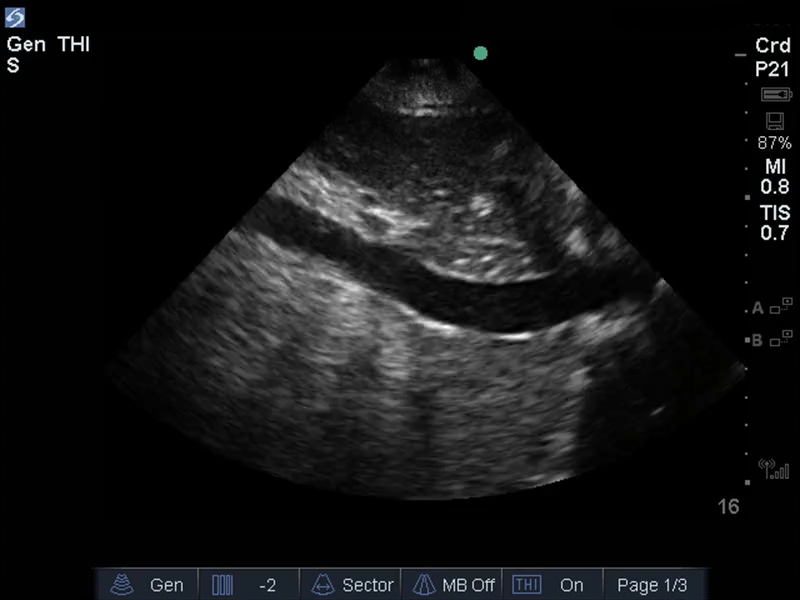

TEE 血流量ステータスの画像